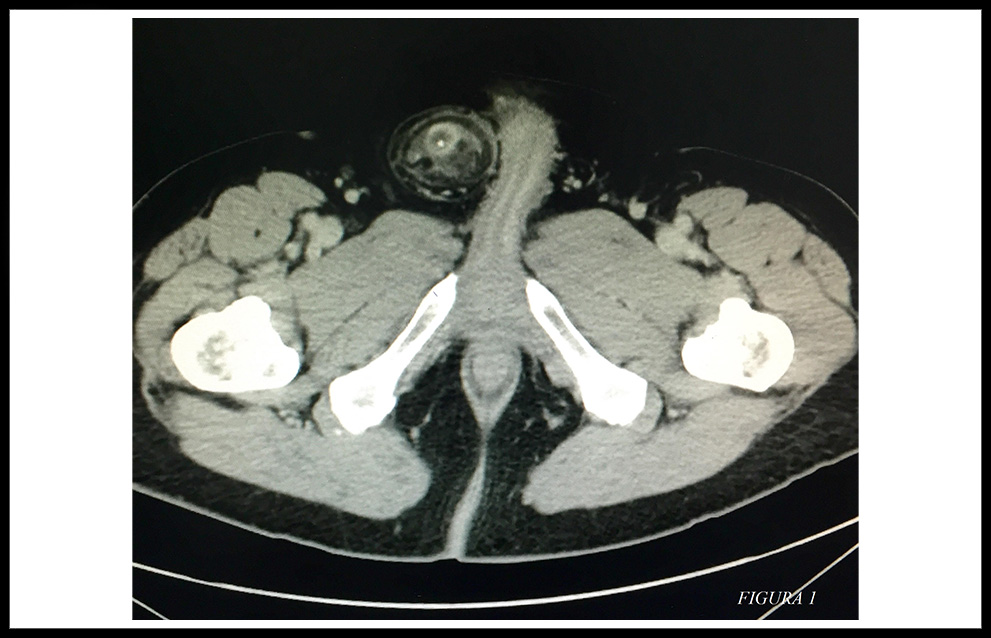

Se completó el diagnóstico mediante un TAC con contraste intravenoso que mostró el apéndice vermiforme engrosado, con origen en el ciego extendiéndose hacia el canal inguinal. (Figura 1 y 2)

Figura 1.